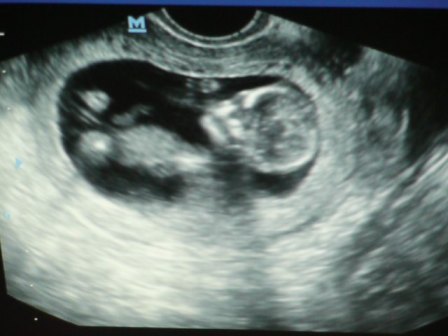

Az újaknak magamról annyit kell tudni, hogy 23 éves vagyok, 4 éve vagyok férjnél! Én már nagyon rég szeretnék babát, viszont férjem és én is még tanulunk, így nem találtuk ésszerűnek, ha most jönne a baba. Titkon magamban reménykedtem, hogy előbb jön, mint ahogy mi tervezzük, és így is lett.

Nagyon örülünk a babánknak és már alig várjuk, hogy megtudjuk fiú vagy lány!!!

Mi kislányt szeretnénk jobban, persze kisfiúnak is örülni fogunk nagyon! A lényeg,h egészséges legyen!